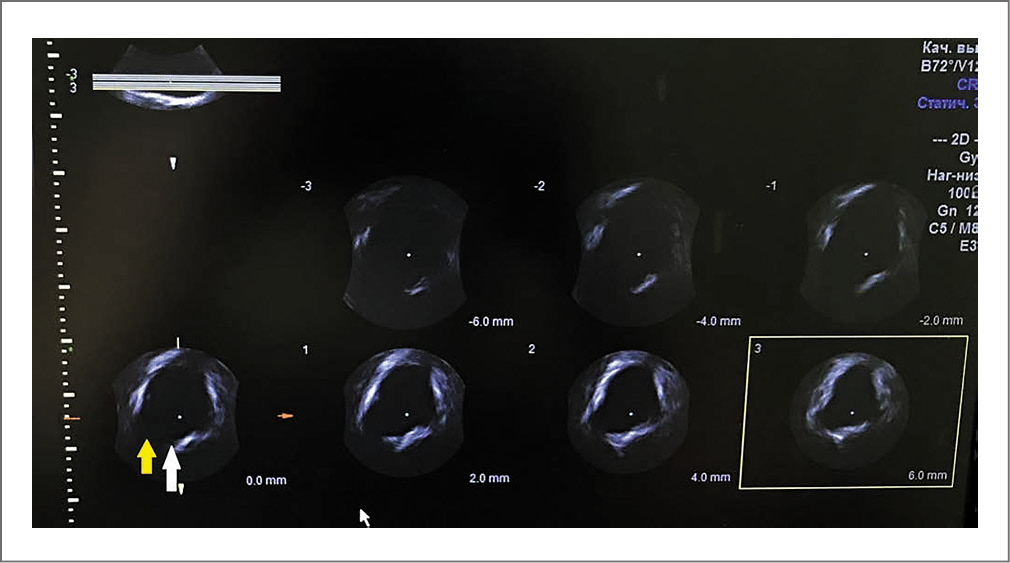

Для определения фасциальных и мышечных дефектов использован режим томографической ультразвуковой визуализации (Tomographic Ultrasound Imaging).

Отмечается асимметричное пролабирование задней стенки мочевого пузыря в трех последовательных томографических срезах. Паравагинальный дефект фасции асимметричный, наиболее выражен справа, также отмечен центральный дефект.

Заключение: сонографические признаки недостаточности мышц ТД (рис. 1), цистоцеле с правосторонним паравагинальным и центральным дефектом фасции (рис. 2), полный правосторонний отрыв m. levatоr ani (рис. 3).

Рис. 2. Трансвагинальное томографическое исследование в аксиальной плоскости. Паравагинальный дефект фасции асимметричный, наиболее выражен справа (желтая стрелка), центральный дефект (белая стрелка).

Рис. 3. Трансперинеальное томографическое исследование в аксиальной плоскости леваторного комплекса. Полный правосторонний отрыв m. levator ani (ЛУИ 2,7 cм; желтые линии).